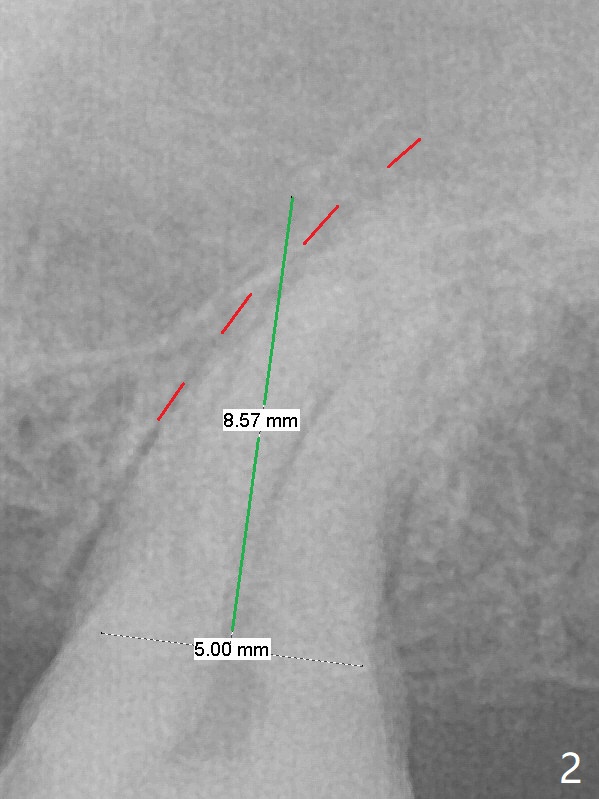

A 58-year-old woman cannot masticate on the left. The tooth #15 has a mesiodistal crack line (now completely split; take preop photo) with mild percussion and mobility I. Pulpal test shows necrosis. Although the roots seem fused and short, they are curved, suggesting bruxism (Fig.1). Use 3 mm Magic Expander to initiate osteotomy (Fig.2 green line) in the mesial slope of the socket (red dashed line). If the bone is dense, switch to Pointed/Lindamann bur. Sinus lift appears to be imminent. Draw blood before the doctor shows up. The implant will be most likely short and fat (5x8.5 mm).